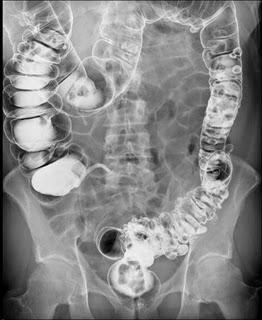

Los tipos especiales de exámenes de rayos X llamados estudios de contraste utilizan tintes con base de yodo o materiales de contraste, como el bario, junto con las radiografías para que los órganos aparezcan en la radiografía y obtener mejores imágenes. Por ejemplo, las radiografías del tracto gastrointestinal inferior, normalmente llamado examen de enema de bario, se emplean para tomar imágenes después de que el intestino se llena con sulfato de bario. Otro estudio, un pielograma intravenoso, usa un colorante especial para examinar la estructura y el funcionamiento del sistema urinario (uréteres, vejiga y riñones).

Radiografías del tracto gastrointestinal inferior (enema de bario): se puede restringir su alimentación durante algunos días antes del estudio. Se usan laxantes, enemas, o ambos, para vaciar el intestino grueso. Para el estudio, usted se acuesta y será sujetado a una mesa. Se toma una serie de radiografías. Luego el líquido de bario se coloca dentro del intestino por medio de un tubo pequeño y blando ubicado en el recto. El líquido se siente frío. Se procede a tomar más imágenes mientras la mesa le inclina a usted en diferentes posiciones. Esto ayuda a que el bario se mueva por los intestinos de modo que puedan verse en las radiografías. Tiene que permanecer acostado inmóvil y contener la respiración cuando se toma cada imagen.

Después del estudio, puede ir al baño para eliminar la solución de bario de los intestinos. (Pueden pasar varios días hasta que esta se haya eliminado por completo. Sus deposiciones pueden ser más secas, más duras y de color claro durante este tiempo).

Para obtener imágenes más claras, por lo general se realiza un examen con “contraste doble”. En este examen se usa una cantidad más pequeña de líquido de bario más espeso. Después que el bario está adentro, se hace ingresar aire en sus intestinos. Esto puede causar una sensación de hinchazón y malestar, junto con la ganas de vaciar los intestinos.